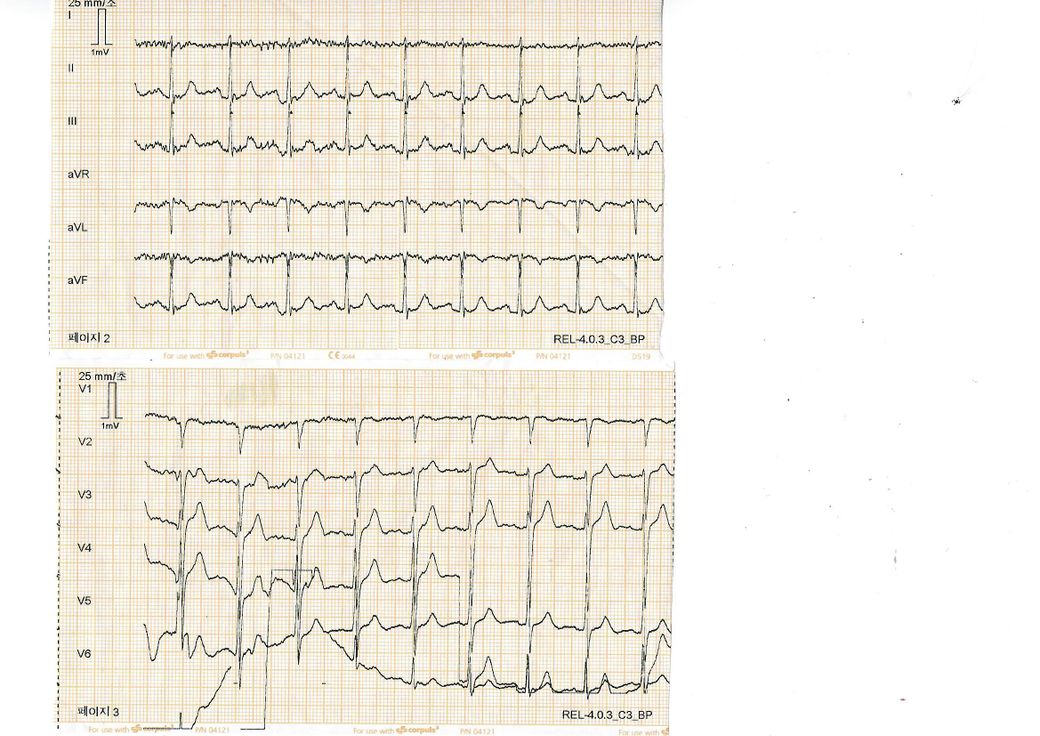

심전도 stemi 해석부탁드립니다. 심전도상에서는 stemi 나왔는데 어떤부분이 상승해서 stemi인지 알고싶습니다 ㅠㅠ

우선 심전도상 파형이 불규칙하여 명확히 촬영된 심전도로 보이진 않으나 빨간색으로 표시해드린 부분에 미약한 STEMI 소견이 관찰되고 있습니다. 다만, 정확한 확인을 위해서는 심전도를 재촬영해보시는 것이 좋을 것으로 생각되며 정확한 판독을 위해서는 검사를 시행한 병원에서 다시한번 판독을 받아보시는 것이 좋겠습니다.

위와 같은 심전도에 가슴통증이 동반되신다면 협심증의 및 심근경색의 위험이 있으므로 즉시 응급실로 내원하실 것을 권고드립니다.